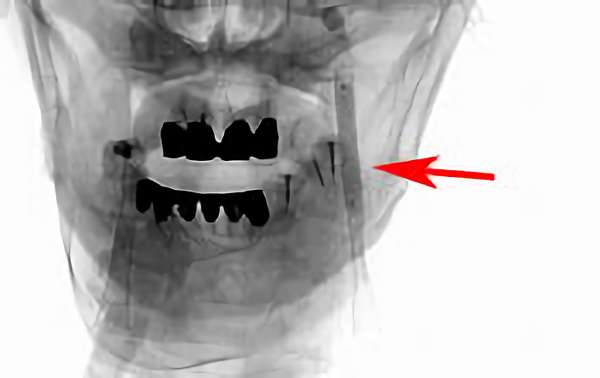

156

'18年6月16日

脳動静脈奇形

60代

院内外来

手術写真

治療

前